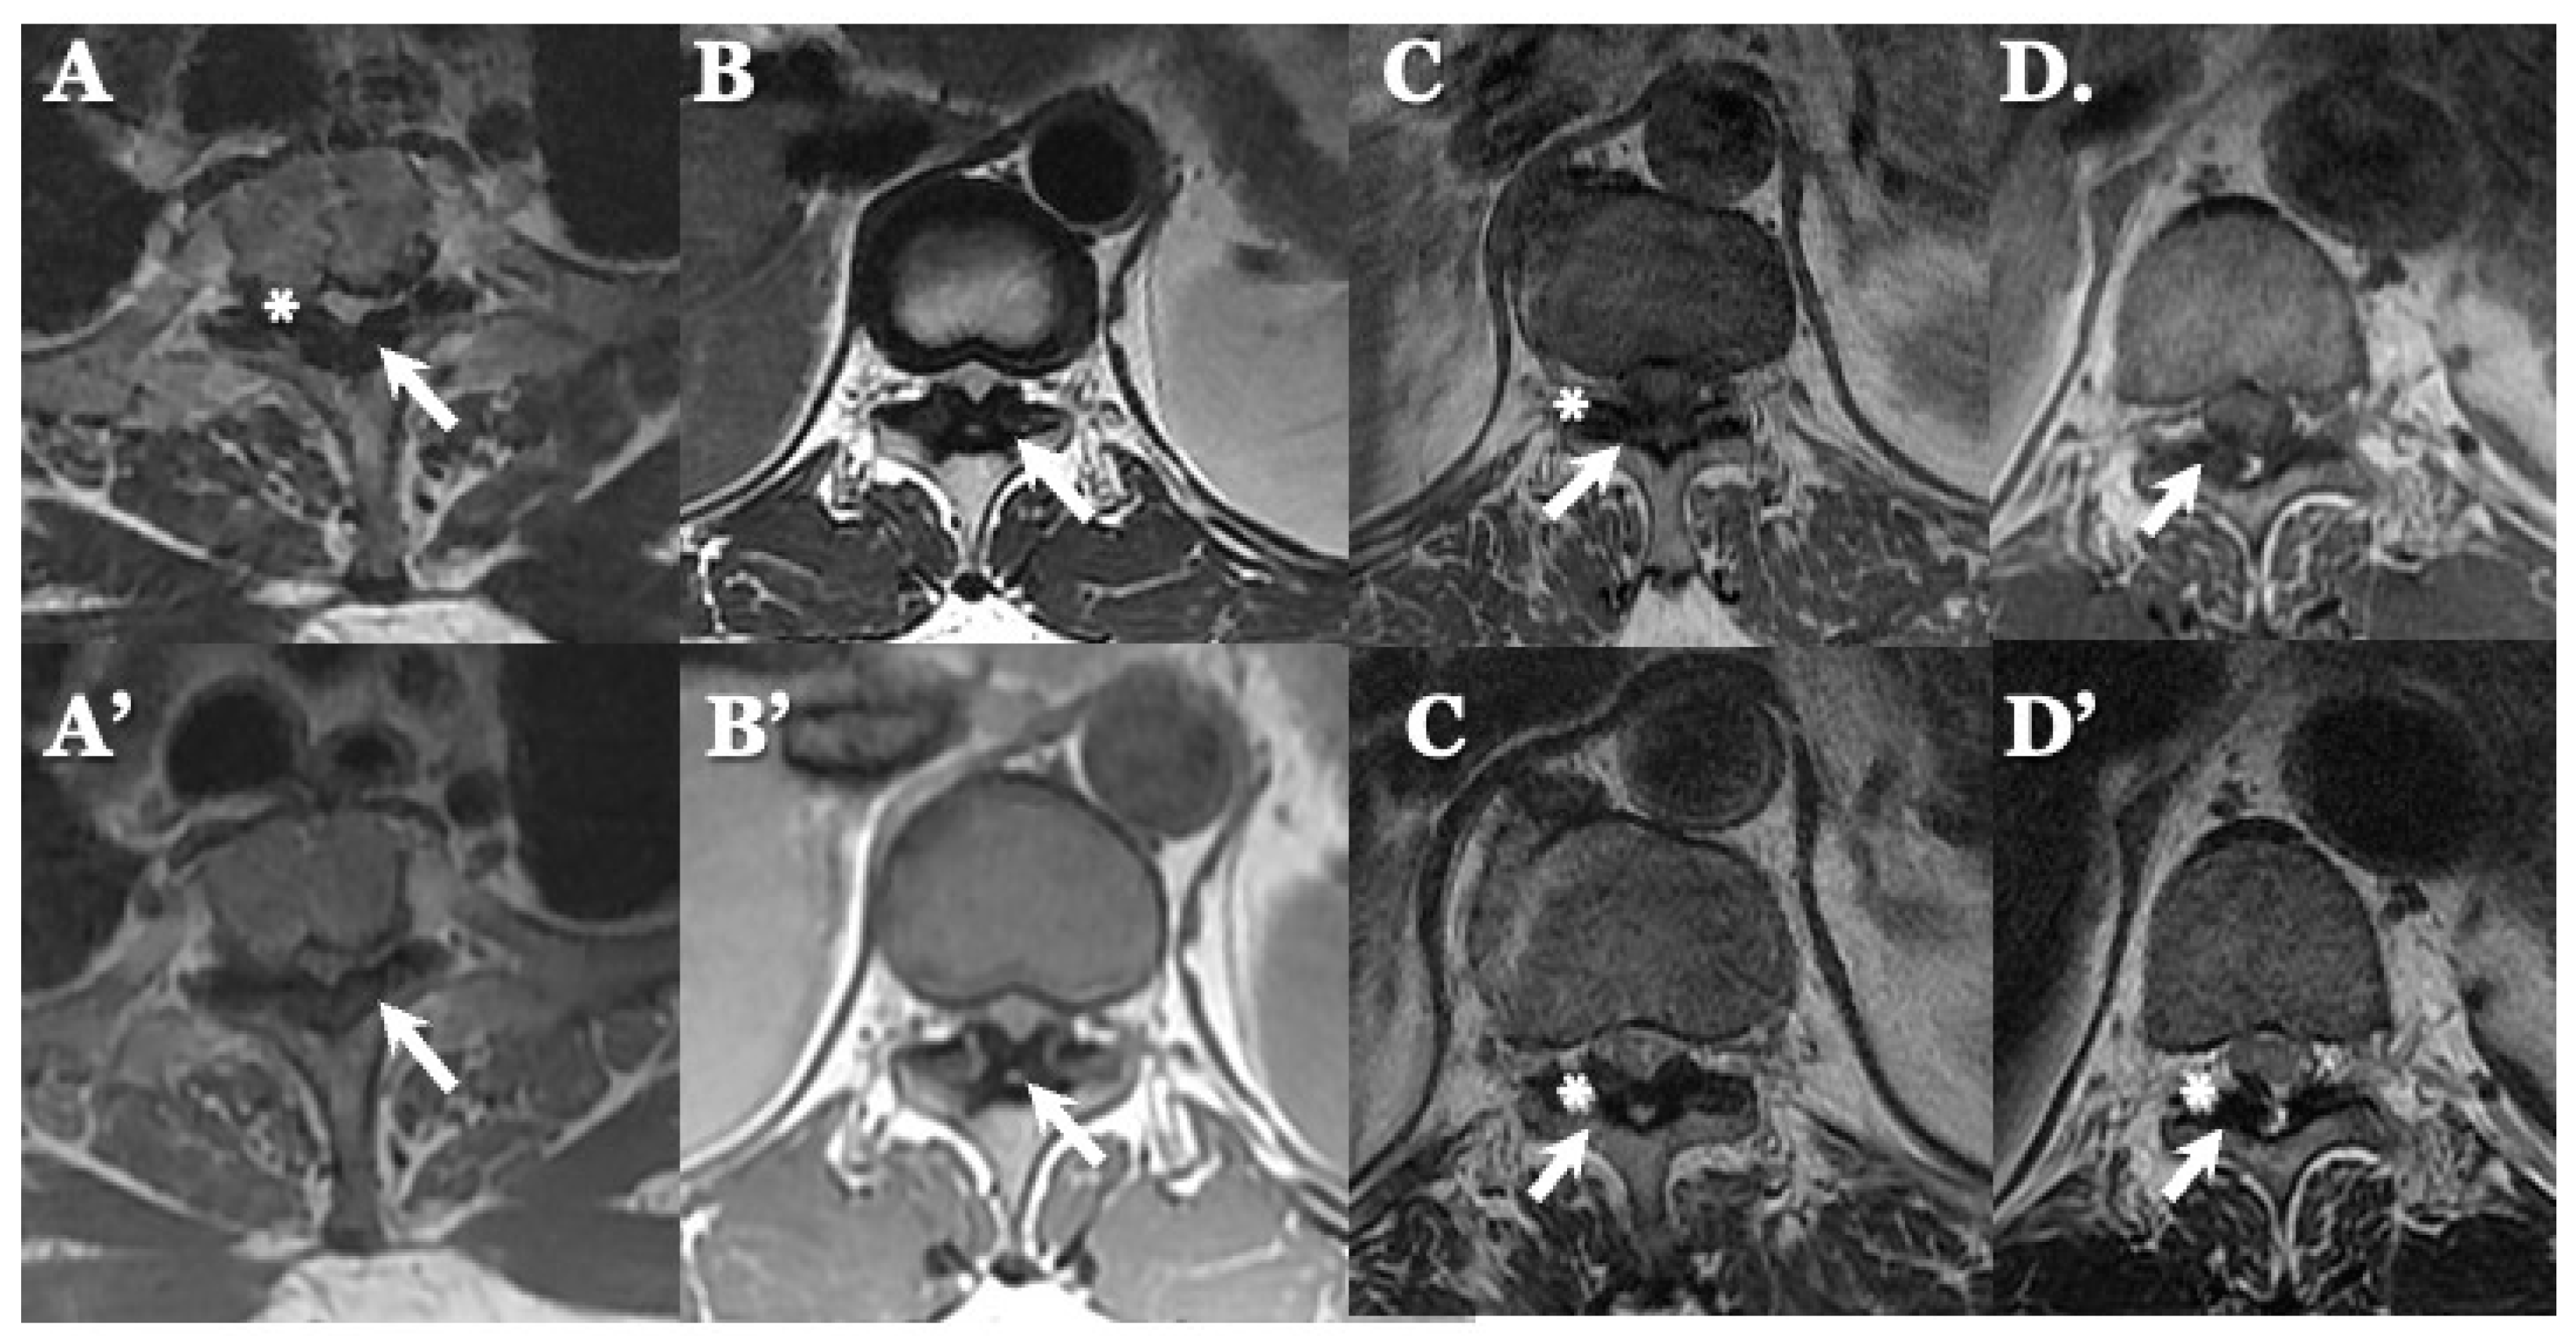

OLF: There were spondylotic changes in 17 cases, developmental narrowing of the spinal canal in 7 cases, disc herniation in 7 cases, ossification of the longitudinal ligament in 4 cases, diffuse idiopathic skeletal hyperostosis (DISH) in 4 cases, and ankylotic spinal hyperostosis (ASH) in 3 cases [31,51,52]. Two-dimensionally reconstructed CT images showed beak-like ossification extending into the intervertebral foramen (Figure 5) (Table 3). MR T1-weighted and T2-weighted images demonstrated low-intensity masses in the dorsal spinal canal, which compressed the spinal cord. In some cases, there were high-intensity spots, suggesting the formation of bone marrow (Figure 6). In three cases, dynamic X-rays of thoraco-lumbar spine demonstrated joint instability (Table 3).

Figure 6.

MR images of OLF. MR T1-weighted axial images (A–D) and T2-weighted axial images (A’–D’) demonstrating low-intensity mass in dorsal spinal canal compressing spinal cord (arrows) and high-intensity spots (white asterisks).

4.2. Comparison of Neuroradiological Findings between CLF and OLF (Figure 3, Figure 4, Figure 5 and Figure 6; Table 3)

OLF: Two-dimensionally reconstructed CT scan images showed beak-like ossification extending into the intervertebral foramen. MR T1-weighted and T2-weighted images demonstrated a low-intensity mass within the dorsal spinal canal compressing the spinal cord. In some cases, the presence of high-intensity spots suggested bone marrow formation (Figure 3 and Figure 4) [18,26,29,30,31]. In some cases, OLF was associated with DISH and ASH, indicating a more generalized ossification pattern (Table 3). Previous reports have reported the association of DISH and ASH in OLF, but the specific features of this association were unclear [51,52]. In both CLF and OLF, spondylotic changes were the most common associated condition, followed by disc herniation and instability. This suggested that chronic micro-movement and mechanical stress (traction, rotation, and compression) to the ligament were contributing factors (Table 3).